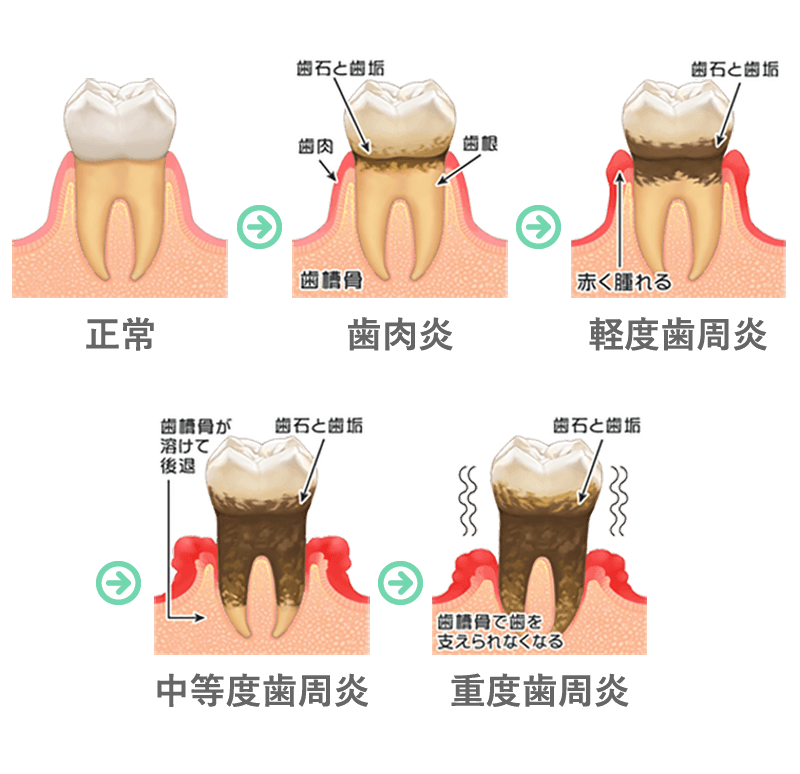

長い期間をかけて徐々に進行し最後には歯が抜けてしまいます。初期の頃は痛みも無く歯ぐきからの出血、口臭程度でほとんど自覚症状がありません。ある程度悪化してから噛めない、腫れている、歯が動く、隙間ができた、歯並びが変わった、などで歯周病だと気づきます。

また、ある日突然、歯周病になるわけではありません。実は、10代から少しずつ進行していき、20数年の歳月をかけて、歯肉をジワジワとゆっくり冒し、歯ぐきから血がでるという自覚症状がでる30代の頃には、もはや歯肉炎・歯周炎になっています。虫歯と違ってほとんど痛みがないため、気がついた時には抜くはめに・・・なんてこともありえる恐い病気なのです。

歯周病に限りませんが、歯周病は悪化すると非常に恐い病気です。歯周病の進行段階は、下の図のように、大きく分けて「歯肉炎→軽度歯周炎→中等度歯周炎→重度歯周炎」という四段階に分けられます。

歯周病の原因はプラークですので、歯周病の重症度によらず、日々の歯磨き(ブラッシング)が最も重要な治療となります。軽度歯周炎で歯石が沈着している場合は、専用の機械・器具を使って歯石を除去します。

中等度以上の進行したケースでは、深いポケット内にある歯石が取り切れないことがあるため、歯肉を切除するなどの歯周外科が必要となることもあります。

重度歯周炎であれば、抜歯せざるをえない時もあります。